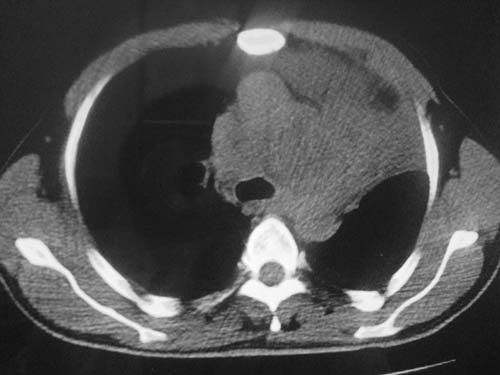

男性39岁,干咳一个月,最近胸憋气短,自己感觉发烧出汗,要求拍ct

图像质量较差请多包含,考虑肺癌,肺结核不除外,大家是否同意这种看法,请各位老师指教

左肺上叶中央型肺癌并阻塞性肺不张。

考虑:左肺上叶中央型肺癌并阻塞性肺不张。左肺下叶囊肿或支扩。

左侧肺癌伴阻塞性肺炎,纵隔转移。

1.左侧肺癌伴阻塞性肺炎,纵隔转移。2.左下肺大泡。3.左下肺感染

纵隔淋吧结肿大

心包积液

双侧胸膜增厚

左肺上叶中央型肺癌并阻塞性肺不张,纵隔淋巴结转移。